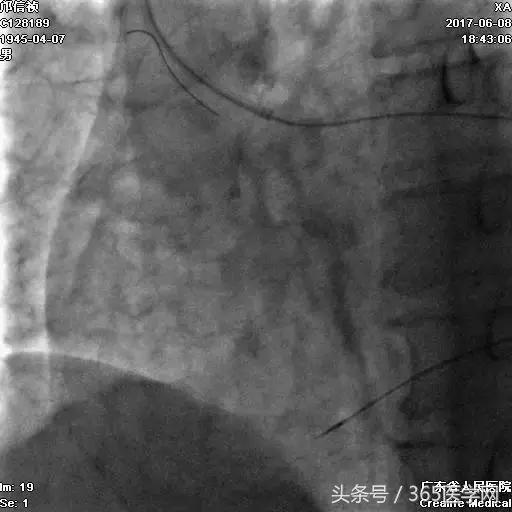

首先:IVUS指导下干预LAD

4.0mm*13mm药物支架